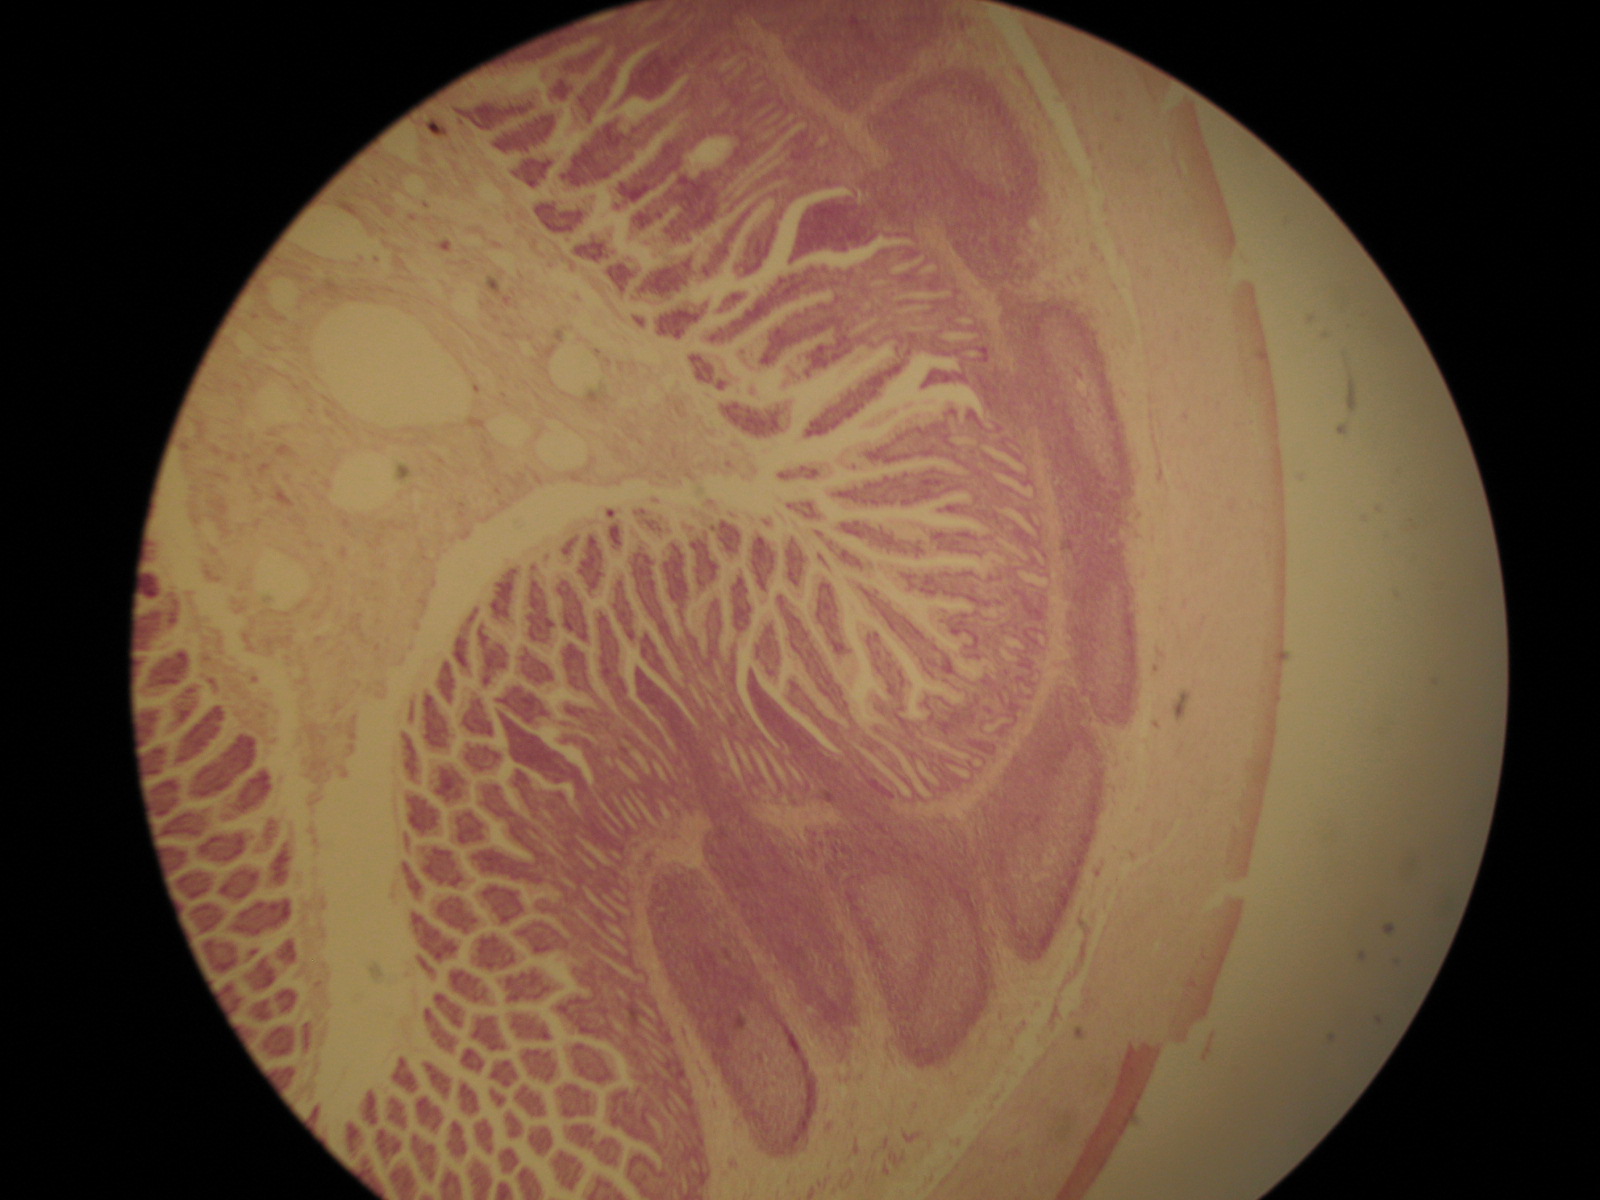

Identify the organ,  | stomach |